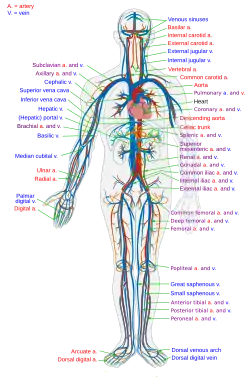

The human circulatory system (simplified). Red indicates oxygenated blood carried in arteries. Blue indicates deoxygenated blood carried in veins. Capillaries join the arteries and veins. | |

The blood circulatory system is a system of organs that includes the heart, blood vessels, and blood which is circulated throughout the entire body of a human or other vertebrate.[1][2] It includes the cardiovascular system, or vascular system, that consists of the heart and blood vessels (from Greek kardia meaning heart, and from Latin vascula meaning vessels). The circulatory system has two divisions, a systemic circulation or circuit, and a pulmonary circulation or circuit.[3] Some sources use the terms cardiovascular system and vascular system interchangeably with the circulatory system.[4]

The network of blood vessels are the great vessels of the heart including large elastic arteries, and large veins; other arteries, smaller arterioles, capillaries that join with venules (small veins), and other veins. The circulatory system is closed in vertebrates, which means that the blood never leaves the network of blood vessels. Some invertebrates such as arthropods have an open circulatory system. Diploblasts such as sponges, and comb jellies lack a circulatory system.

The circulatory system includes the heart, blood vessels, and blood.[2] The cardiovascular system in all vertebrates, consists of the heart and blood vessels. The circulatory system is further divided into two major circuits – a pulmonary circulation, and a systemic circulation.[8][1][3] The pulmonary circulation is a circuit loop from the right heart taking deoxygenated blood to the lungs where it is oxygenated and returned to the left heart. The systemic circulation is a circuit loop that delivers oxygenated blood from the left heart to the rest of the body, and returns deoxygenated blood back to the right heart via large veins known as the venae cavae. The systemic circulation can also be defined as two parts – a macrocirculation and a microcirculation. An average adult contains five to six quarts (roughly 4.7 to 5.7 liters) of blood, accounting for approximately 7% of their total body weight.[9] Blood consists of plasma, red blood cells, white blood cells, and platelets. The digestive system also works with the circulatory system to provide the nutrients the system needs to keep the heart pumping.[10]

The blood vessels of the circulatory system are the arteries, veins, and capillaries. The large arteries and veins that take blood to, and away from the heart are known as the great vessels.[14]